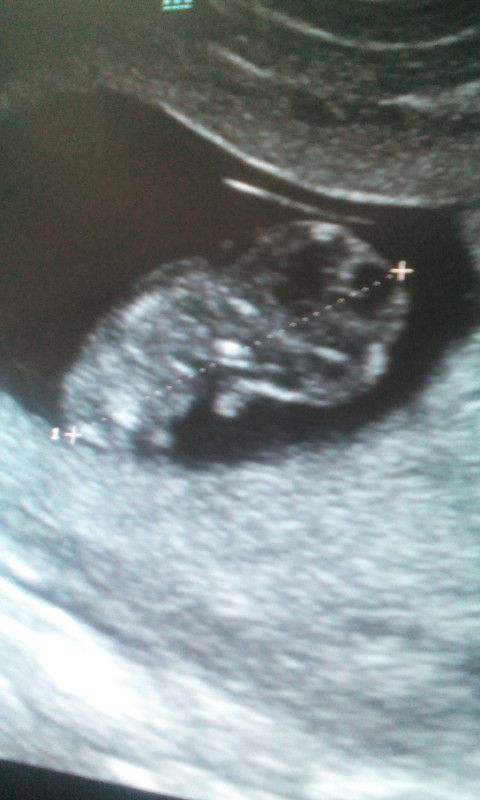

Ванилька, На 5неделе нет.только плодное яичко.а на 8неделе видно было. А вот это на 10 неделе сделала уже